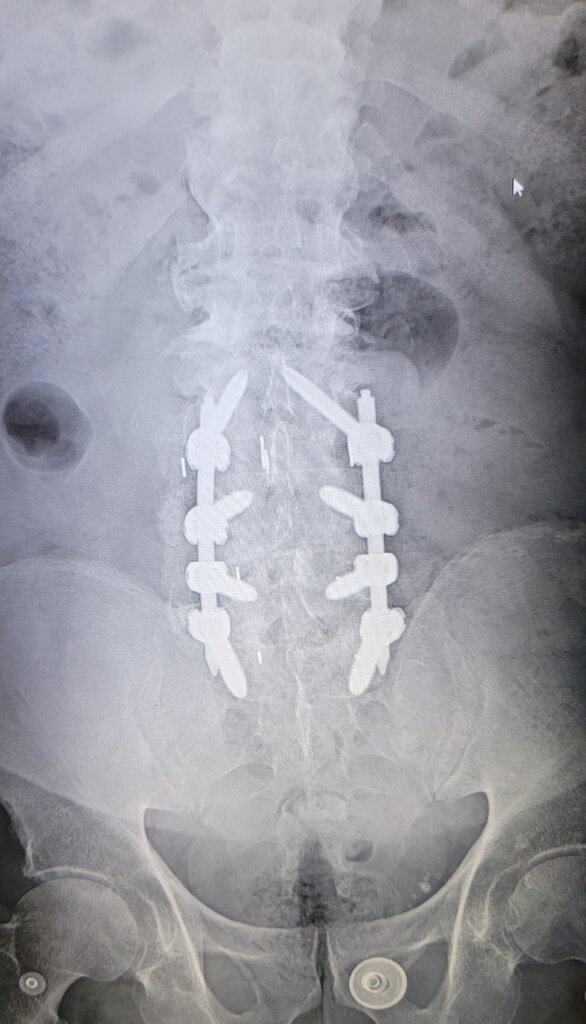

Just did a 2 hour implant with 2 leads. Prior surgery T7-8, T11-L1, L2-S1.